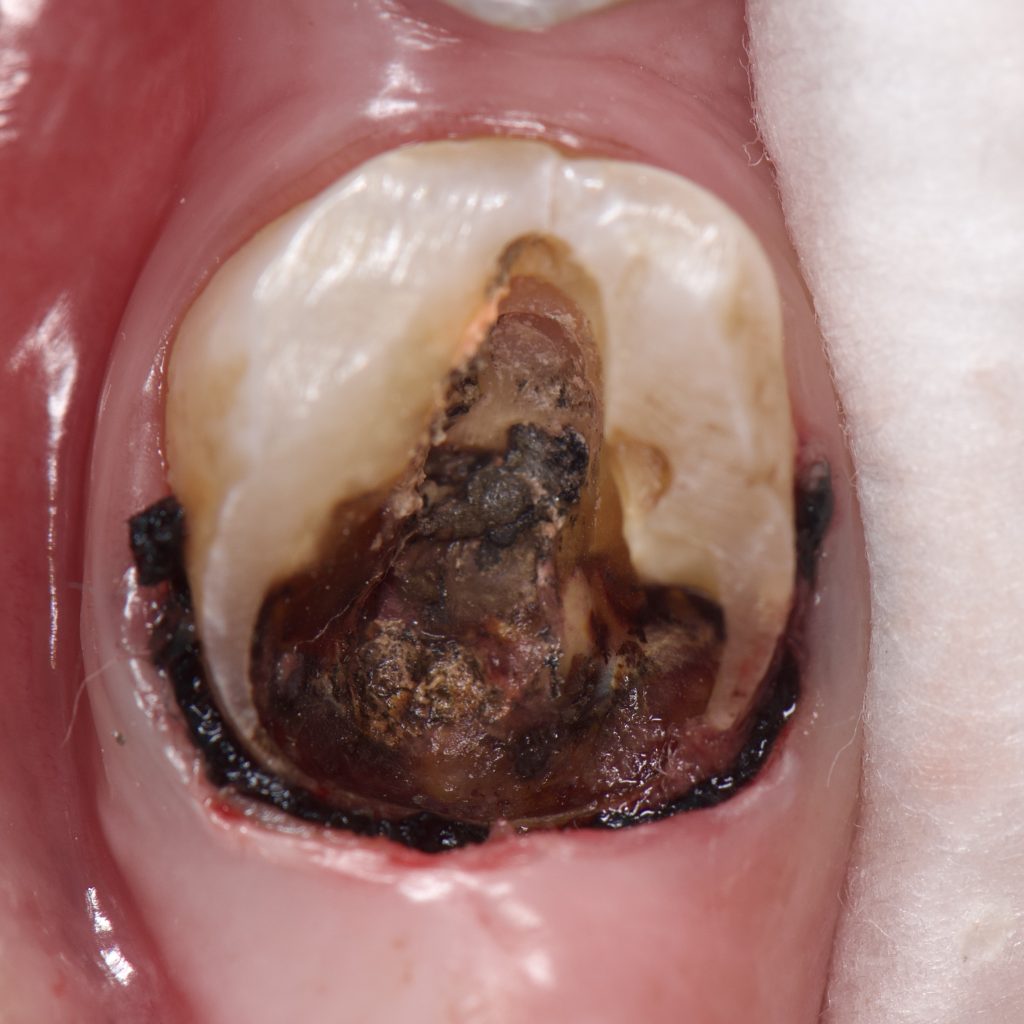

– Treatment began with removing the old amalgam filling and cleaning the tooth from the remaining caries and excess Gutta percha

– Deep margin elevation done with gold standard Bond and Ap-x composite